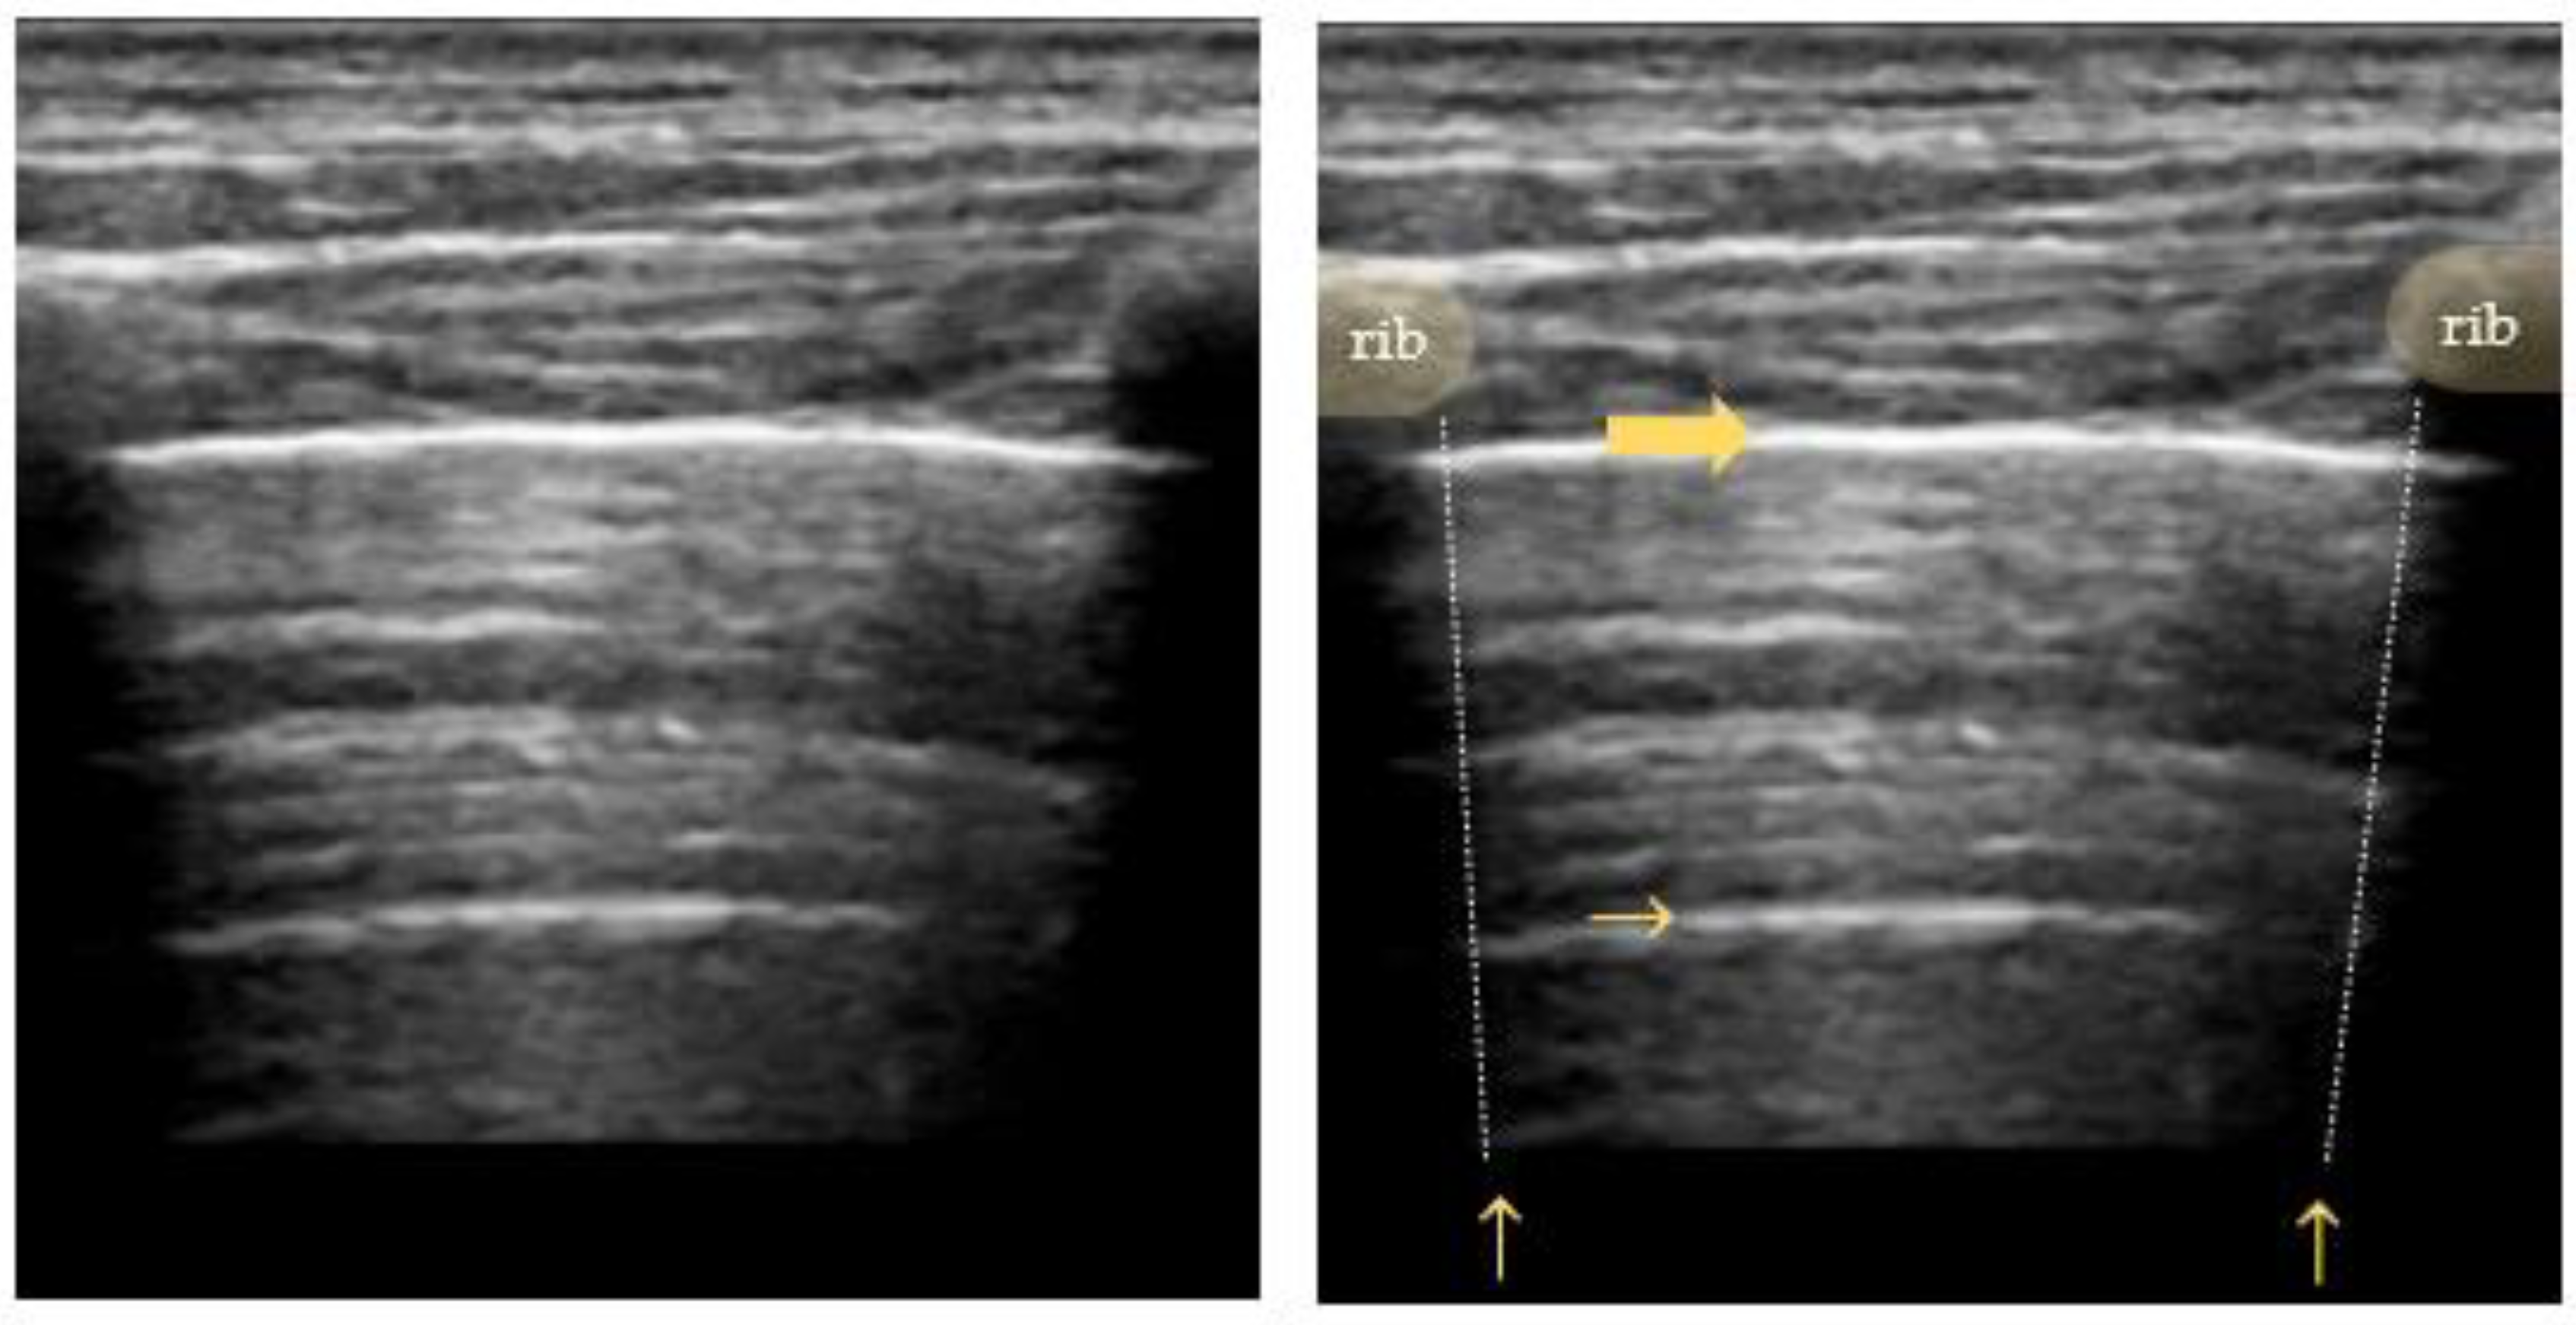

4.1. Pneumothorax

- Absence of lung sliding;

- Absence of B-lines;

- Absence of lung pulse;

- Presence of lung point(s) [42].